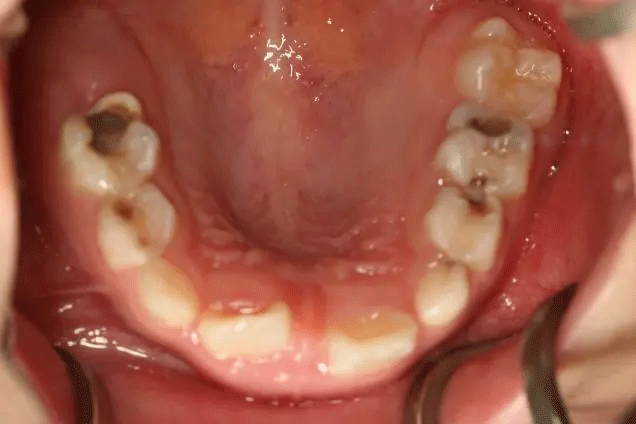

在門診中發(fā)現(xiàn)

來口腔科檢查的孩子

有些牙齒都已經(jīng)爛得很嚴(yán)重了

甚至牙齒幾乎都爛光僅剩下牙根

孩子不喊疼,家長很少會帶來看牙